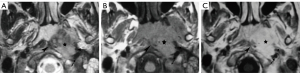

Paragangliomas have characteristic CT and MRI appearances based on their hypervascularity. They are usually homogeneously or heterogeneously hyperdense or hyperintense after contrast enhancement, with incorporation of adjacent arteries on CT and MRI (Figures 10-12) (12). On MRI, serpentine and punctate areas of signal void representing high vascular flow are interspersed with areas of high signal intensity caused by slowly flowing blood. This “salt-and-pepper” pattern is seen in all lesions greater than 2 cm in maximal dimension (Figure 11) (23-25). Carotid body tumors (paragangliomas of the carotid body) splay the ICA and the external carotid artery (ECA) and may encase the ICA and ECA (Figure 10), whereas vagal paragangliomas displace both ICA and ECA anteromedially, separating these vessels from the IJV (Figure 11). Paragangliomas may be multicentric and can manifest as unilateral or bilateral lesions, either simultaneously or sequentially. Only a very low percentage of 3% of paragangliomas will undergo malignant transformation (25). The presence of local lymph node involvement, distant metastases, or extensive local invasion will establish the malignancy of a paraganglioma.